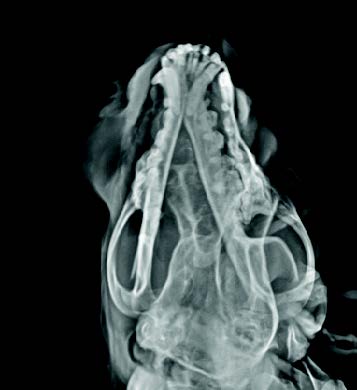

影像学表现为溶骨性膨胀性病变,伴增生性骨膜反应,边缘不规则,骨膜反应呈点状至柱状(图3)。肿瘤起始于鼻孔末端延伸至眼眶区域,与正常骨组织的过渡区界限不清。额骨、鼻骨及上颌骨可见明显破坏,提示为侵袭性骨病变。

图3. X线片示溶骨性膨胀性病变,伴增生性骨膜反应,边缘不规则,骨膜反应呈点状至柱状。

本例报告了一例12岁母犬,其前鼻骨区域出现一巨大组织细胞瘤,直径约10厘米,病程进展迅速。该病例在临床、影像学及病理学上均表现出一定复杂性,尤其在老年犬中较为罕见,增加了诊断难度。初步影像学检查显示该肿瘤伴随明显的骨破坏和骨膜反应,提示为侵袭性病变,因此需与多发性骨髓瘤、骨肉瘤、鳞状细胞癌等恶性肿瘤鉴别。